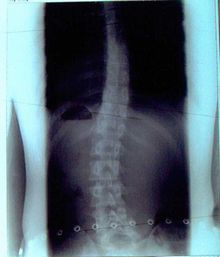

症例12)

初診18歳でも体操で大きく度数の改善と身長も2センチ伸びた。

�@平成19年4月初診 18歳 男子受験生

14度-25度 身長168センチ

�A平成20年8月 医学部学生となっており、改善しお礼に来院。

12度-14度 身長170センチ・成人として安全度数です。体操の継続により受験を突破し改善と身長も伸びた。終了です。

彼は改善と身長が伸びたことを大変喜んでいました。

君が整形外科医になったらどうすると質問すると私は自分で体験しましたので体操を指導しますと話してくれました。

ハキハキとした大変な好青年でした。

平成19年4月

初診レントゲン

平成20年8月

レントゲン

(14度)-25度

12度-14度